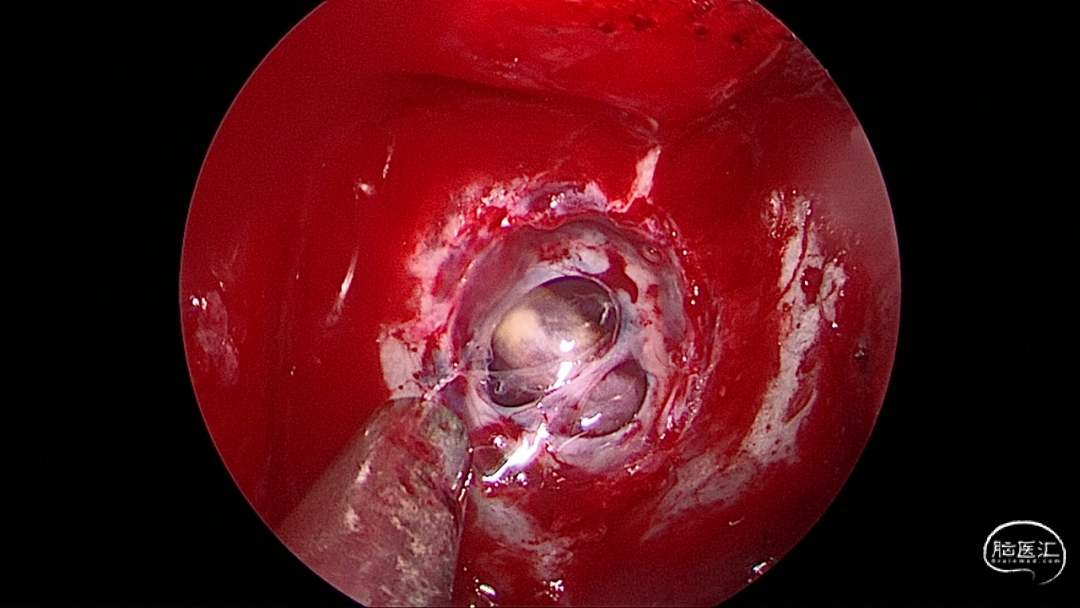

带蒂粘膜瓣修复

那么,至此该患者所有的疑团均已解开,是一个生长于斜坡的微小脊索瘤侵蚀了骨质及硬膜,导致出现自发的脑脊液鼻漏,经过我们微创手术,目前患者已经平稳出院,恢复正常生活。

脊索瘤是一种罕见的、生长缓慢的、具有局部侵袭性及破坏性的肿瘤。脊索瘤是低度恶性的肿瘤,有高度的局部增长倾向。大部分脊索瘤侵犯骨质,生长于硬膜外,在肿瘤增大到一定程度后会侵犯以及突破硬膜进入颅内。此例患者肿瘤微小即侵犯了硬膜,在常规MR上不显影,较为少见,临床中容易忽略此类疾病,也提示我们在排查脑脊液漏原因的时候,一定要把肿瘤性因素考虑在内,避免遗漏。